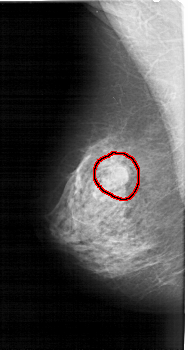

A_1396_1.LEFT_MLO

LEFT_MLO LINES 5236 PIXELS_PER_LINE 2806 BITS_PER_PIXEL 12 RESOLUTION 43.5 OVERLAY

FILE: A_1396_1.LEFT_MLO.OVERLAY

TOTAL_ABNORMALITIES 1

ABNORMALITY 1

LESION_TYPE MASS SHAPE ROUND MARGINS OBSCURED

ASSESSMENT 4

SUBTLETY 3

PATHOLOGY BENIGN

TOTAL_OUTLINES 1

BOUNDARY